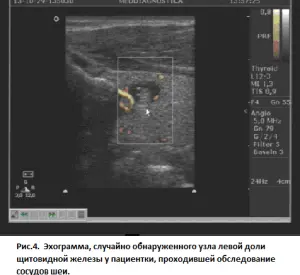

В нашей клинике мы очень часто исследуем сосуды шеи или шейный отдел позвоночника, и нередко, в поле зрения, попадают измененная щитовидная железы, при этом, она может быть увеличена, содержать узлы и кисты, в ней могут определяться признаки воспалительного процесса и, зачастую, на вопрос «Находитесь ли вы под наблюдением по поводу щитовидной железы?» приходится слышать: « Нет, она ведь меня не беспокоит». Грубо говоря, у пациента складывается ошибочное мнение: не болит – значит все в порядке. Но в том то и коварность заболеваний данного органа, что они крайне редко вызывают болевые ощущения.

Исследование занимает от 15 до 30 мин, никакой специальной подготовки не требуется. Как и все другие ультразвуковые исследования, абсолютно безопасно для пациента (возможность обследования беременных и детей). При этом оцениваются размеры щитовидной железы, однородность ее структуры, наличие кист и узлов в ее структуре с подробным описанием и измерениями образований в 3-х плоскостях (позволяет следить за возможным ростом образований в динамике), оценка кровотока щитовидной железы в целом и внутри образований в частности.